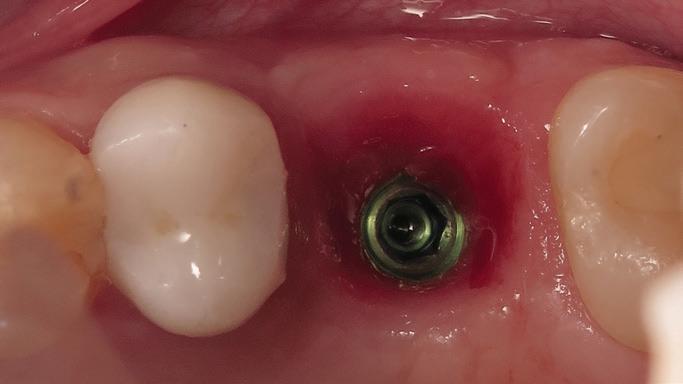

Tooth replacement from extraction to restoration. 3. Second-stage and impression procedures

The third part of this series reviews uncovering of implants that were buried in a 2-stage approach, provisionalization of the implant, and impression and scanning techniques.1 These techniques are all crucial for the final restorative outcome of the implant. The uncovering and second-stage procedures set the foundation for the shape and position of the soft tissue, which are very important esthetic factors. This information must also be properly transferred to the laboratory via a highly accurate impression so the laboratory has as much information as possible. If these steps are done properly, the result will be implant crowns that are easy to seat, biologically ideal, and esthetically pleasing.